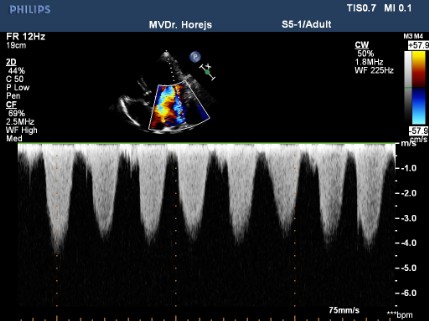

Dilatační kardiomyopatie